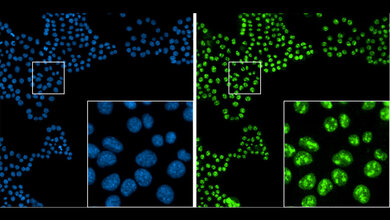

Doch auch bei der Diagnostik geht es mit Riesenschritten voran. Neben den neuen Möglichkeiten in der Bildgebung ist hier beispielsweise Liquid Biopsy ein Schlagwort. Die Nukleinsäureanalytik zum Nachweis von Tumorzellen und Tumor-DNA sorgt für Furore.